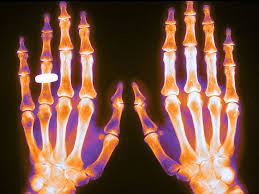

El objetivo de esta Folia.doc es brindar recomendaciones basadas en evidencia sobre prevención y tratamiento de osteoporosis considerando la eficacia, efectividad y segu­ridad de los medicamentos disponibles. Estas recomen­daciones son válidas tanto para el equipo de salud de atención primaria como para especialistas en el segundo nivel de atención, ya que el tema de prevenir y tratar os­teoporosis y fracturas por fragilidad los involucra a todos. FoliaDoc , Fundación Femeba, 16 de octubre de 2024